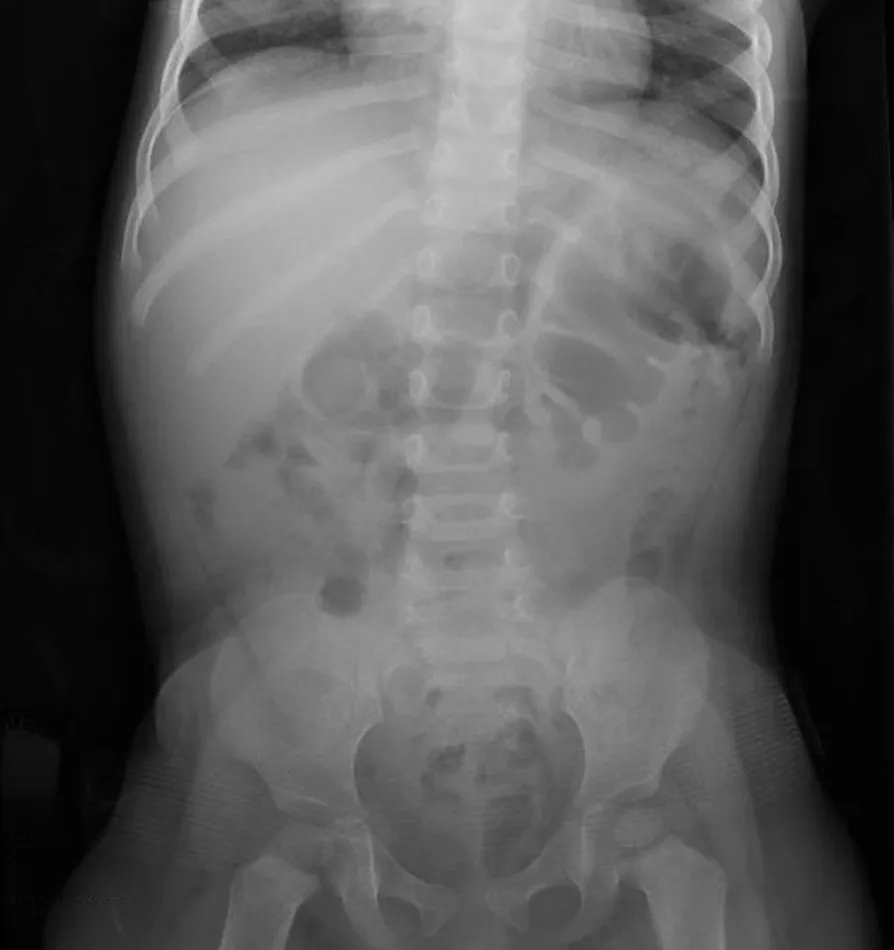

폐색의 정확한 원인과 위치를 알아내기 위해서는 복부 CT 검사가 필수적입니다. 또한, 장의 위치와 그 기능적 상태를 더 자세히 알아보기 위해 조영제를 사용하여 소장의 엑스레이 촬영을 시간대별로 수행하기도 합니다.